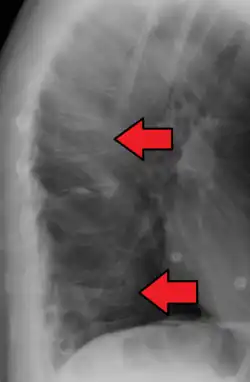

Compression fracture of the fourth lumbar vertebra post falling from a height. -